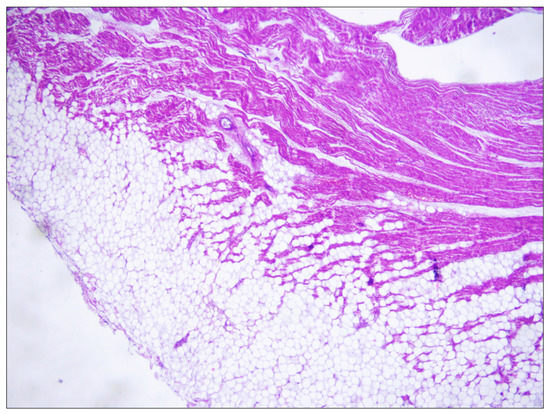

2. Cases Presentation

- Cohle, S.D.; Suarez-Mier, M.P.; Aguilera, B. Sudden Death Resulting from Lesions of the Cardiac Conduction System. Am. J. Forensic Med. Pathol. 2002, 23, 83–89. [Google Scholar] [CrossRef] [PubMed]

- Bharati, S.; Lev, M. Sudden Death in Athletes—Conduction System: Practical Approach to Dissection and Pertinent Pathology. Cardiovasc. Pathol. 1994, 3, 117–127. [Google Scholar] [CrossRef]

- Bharati, S.; Lev, M. Conduction System Findings in Sudden Death in Young Adults with a History of Bronchial Asthma. J. Am. Coll. Cardiol. 1994, 23, 741–746. [Google Scholar] [CrossRef]

- Bharati, S.; Lev, M. Cardiac Conduction System Involvement in Sudden Death of Obese Young People. Am. Heart J. 1995, 129, 273–281. [Google Scholar] [CrossRef]

- Ottaviani, G.; Alfonsi, G.; Ramos, S.G.; Buja, L.M. Sudden Unexpected Death Associated with Arrhythmogenic Cardiomyopathy: Study of the Cardiac Conduction System. Diagnostics 2021, 11, 1323. [Google Scholar] [CrossRef]

- Rogers, A.; Taylor, R.; Poulik, J.; Shehata, B.M. Histopathology of the Conduction System in Long QT Syndrome. Fetal Pediatr. Pathol. 2021, 10, 2562–2585. [Google Scholar] [CrossRef]